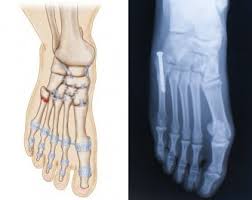

The sutures in the small incision will need to be removed after 10 to 14 days. See more ideas about fracture healing, jones fracture, fracture. These are notorious for very slow healing. What is the recovery time of a broken ankle? Do you have a jones fracture of the 5th metatarsal? Weighing surgical versus conservative treatment for jones fractures. Well find out exactly how to get this bone feeling better! This is an ap view of a percutaneous jones fracture surgery. Outside of the foot pain can be improved with a few simple treatment. While people can relate to a stubbed toe or sprained ankle; Surgical treatment of femoral neck fracture. 5th metatarsal fracture recovery time: A jones fracture occurs in a region known as the the incision required to repair a jones fracture is small and the surgery can be done as an outpatient procedure under general or local anesthesia.

Intramedullary Screw Fixation Of Proximal Fifth Metatarsal Fractures In Athletes from www.scielo.br Lengthy healing times and risk of refracture may be reasons for surgical repair in these fractures. A foot can be broken in many places learn about the jones fracture, what types of treatments are available, and if jones fracture surgery is the best treatment option. Patient may be in a removable boot after surgery for a week or two at the direction of the physician. Jones fractures are named after sir robert jonestrusted source , an orthopedic surgeon who in 1902 reported on his own injury and the injuries of several people he. Do you have a jones fracture of the 5th metatarsal? Jones fracture surgery recovery on mainkeys. A jones fracture is a break between the base and middle part of the fifth metatarsal of the foot. Yet surgery is not always necessary.

A jones fracture is a break between the base and middle part of the fifth metatarsal of the foot. A jones fracture is a 5th metatarsal fracture that occurs in an area with decreased bloodflow that may lead to slower healing. Remember that below is a guide to recovery and that everyone heals at different rates and some people do take longer. Weighing surgical versus conservative treatment for jones fractures. Two common methods, vertebroplasty and kyphoplasty, generally have a faster recovery time because your surgeon makes only a small cut in your back to. Zone 2 fractures are known as jones fractures. Well find out exactly how to get this bone feeling better! Have foot pain at some time in their lives. What is a lisfranc fracture? Jones fracture surgery recovery on mainkeys. This is another way of saying a jones fracture. Sanders type 3 break with surgery about 1 week later. It can take time to heal because there is limited blood flow to the area.